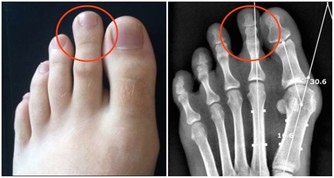

▲(圖/翻攝自google)